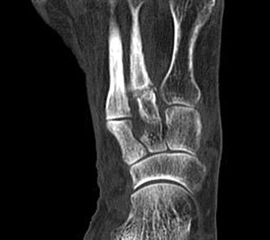

Die Osteochondrosis dissecans tali (OD) ist definiert als lokalisierte Pathologie der Gelenkfläche des Talus, die zur Abtrennung eines kartilaginären Fragmentes und subchondralen Knochens führen kann 93. Es existieren am Körper 3 Prädilektionsstellen für die Entwicklung einer OD mit unterschiedlicher Häufigkeit: Femurkondylen 75%, Talus 12% und Capitulum humeri 12%, sowie sonstigen Lokalisationen 1%. Abhängig vom Zeitpunkt des Auftretens unterscheidet man die juvenile Form (offene Wachstumsfuge) von der adulten Form (geschlossene Wachstumsfuge) (Dotti 2002).

Nach Dotti sind am Talus vorrangig die posteromediale und die anterolaterale Talusschulter betroffen. Die Ätiologie der OD an der anterolateralen Talusschulter scheint vermehrt traumatisch/repetitiv mikrotraumatisch zu sein, die der posteromedialen Talusschulter vermehrt idiopathisch.

Die Stadieneinteilung nach Berndt und Harty umfasst 4 Stadien und ist unabhängig von der Lokalisation der OD anwendbar 94.

Die Stadieneinteilung nach ARCO (Association Internationale de Recherche sur la Circulation Osseuse) berücksichtigt die Kombination aus MRI-Zeichen, Nativradiologie und Knochenszintigraphie 95.

Die Therapie orientiert sich an der Stadieneinteilung und Lokalisation der OD, sowie am Lebensalter des Patienten. Eine aktuelle Metaanalyse zur OD am Talus 96 zeigt ein Durchschnittsalter von 28 Jahren, bei jüngeren Patienten ist ein günstigerer Verlauf zu erwarten. Die höchste Rate an Spontanheilungen wird bei Kindern beobachtet.

Als Alternative zu operativen Maßnahmen wird bei frühen Stadien der OD auch der Einsatz fokussierter Stoßwellentherapie diskutiert, wenngleich es bislang wenig klinische Studien zur ESWT bei OD am Talus gibt.

Die ESWT wird in der Regel in einer Sitzung unter Leitungs– oder Allgemeinanästhesie durchgeführt, wobei nach Empfehlungen der DIGEST eine mittlere Energieflussdichte von 0,35mJ/mm² und eine Anzahl von 2500 Impulsen empfohlen wird. Bei hochenergetischer Behandlung (>0,5mJ/mm²) kann eine Schädigung des Knorpels nicht sicher ausgeschlossen werden 97.

Nach der Behandlung wird eine Entlastung für ca. 2 - 6 Wochen empfohlen. MRT-Kontrollen sind nach 3, 6 und 12 Monaten sinnvoll.

Aufgrund der Datenlage kann die Anwendung der ESWT bei osteochondralen Läsionen des Talus in frühen Stadien (1 und 2 nach ARCO) erwogen werden. Für eine Therapieempfehlung sind allerdings weitere Studien, insbesondere zur Therapie der OD des Talus zwingend erforderlich. Aufgrund der technischen Schwierigkeit der Behandlung bei teilweise schlechter Erreichbarkeit der Läsion, sollte diese Indikation erfahrenen Anwendern vorbehalten bleiben.